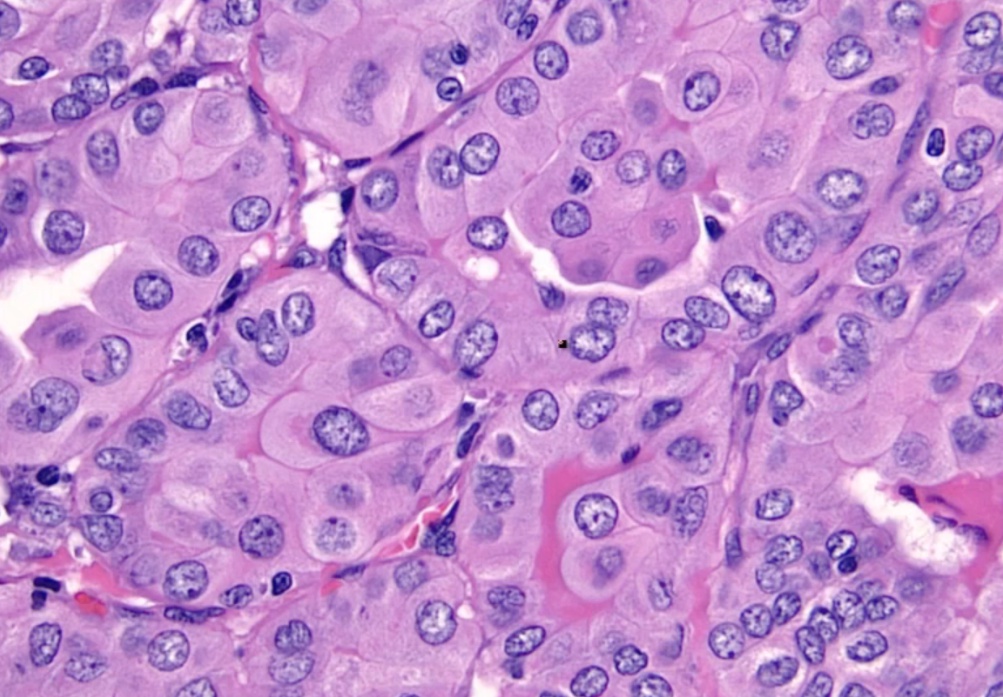

_Histologic findings include:

Diffuse hypertrophy and hyperplasia of thyroid follicular epithelial cells

Colloid appears pale with scalloped (moth-eaten) margins due to increased colloid absorption.

Lymphocytic infiltrate leads to germinal centers in the thyroid (more commonly seen in Hashimoto thyroiditis). **